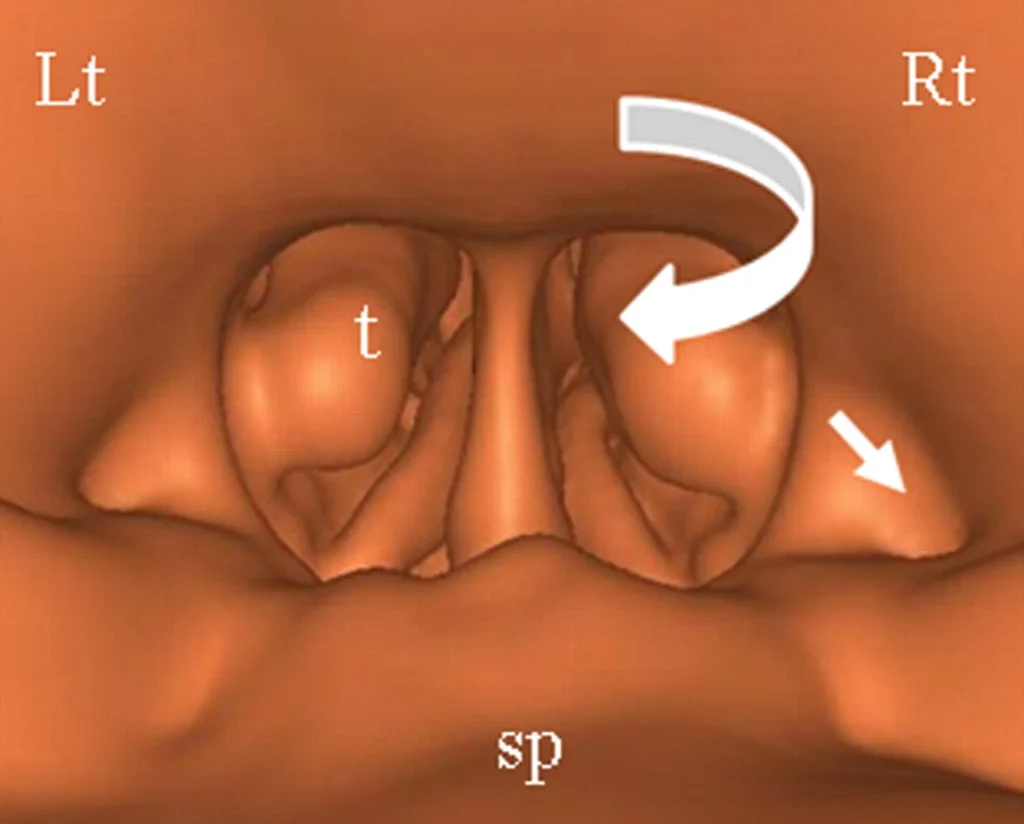

CT Endoscopy & Virtual Bronchoscopy in Navi Mumbai | Henotic Diagnostics

Looking for CT Endoscopy and Virtual Bronchoscopy in Kharghar? Henotic Diagnostics offers advanced, non-invasive 3D imaging of the airways and gastrointestinal tract. Virtual Bronchoscopy helps detect lung tumors, airway obstructions, and tracheal issues. In addition, CT Endoscopy (Virtual Colonoscopy) aids in diagnosing polyps, tumors, and intestinal conditions without invasive procedures. Furthermore, our expert radiologists provide detailed reports with minimal discomfort and low radiation. Available in Kharghar, Panvel, Belapur, Nerul, Vashi, and Navi Mumbai. Book your CT scan today!